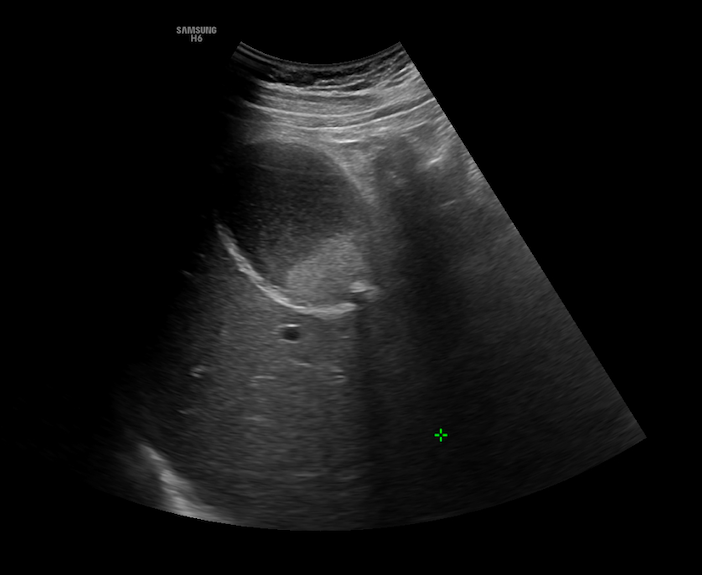

Se realiza una exploración abdominal, donde se objetiva distensión de la vesícula biliar, con un diámetro longitudinal de 10 cm, y engrosamiento de la pared de 4 mm (figura 1), abundante barro biliar (figura 2) y la presencia de una litiasis en cuello vesicular (figura 3). Murphy ecográfico positivo. Doppler negativo, sin dilatación de la vía biliar (figura 4). No líquido perivesicular. Resto de rastreo sin alteraciones.